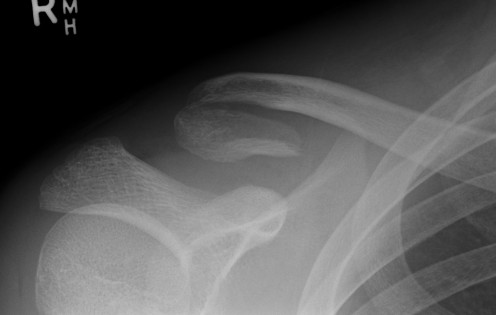

Hook Plate

Mechanically secure

Needs to be removed

- subacromial impingement

- acromial erosion

- shoulder stiffness

- 36 patients with displaced distal clavicle fractures treated with hook plate

- 95% union rate

- mean time to union 3 months

- hook plate removed in 92%

- 2 patients presented with late falls and fractures medial to the plate

- 35 patients with displaced distal clavicle fractures treated with hook plate

- 100% union rates

- 23% shoulder stiffness

- 17% subacromial erosion